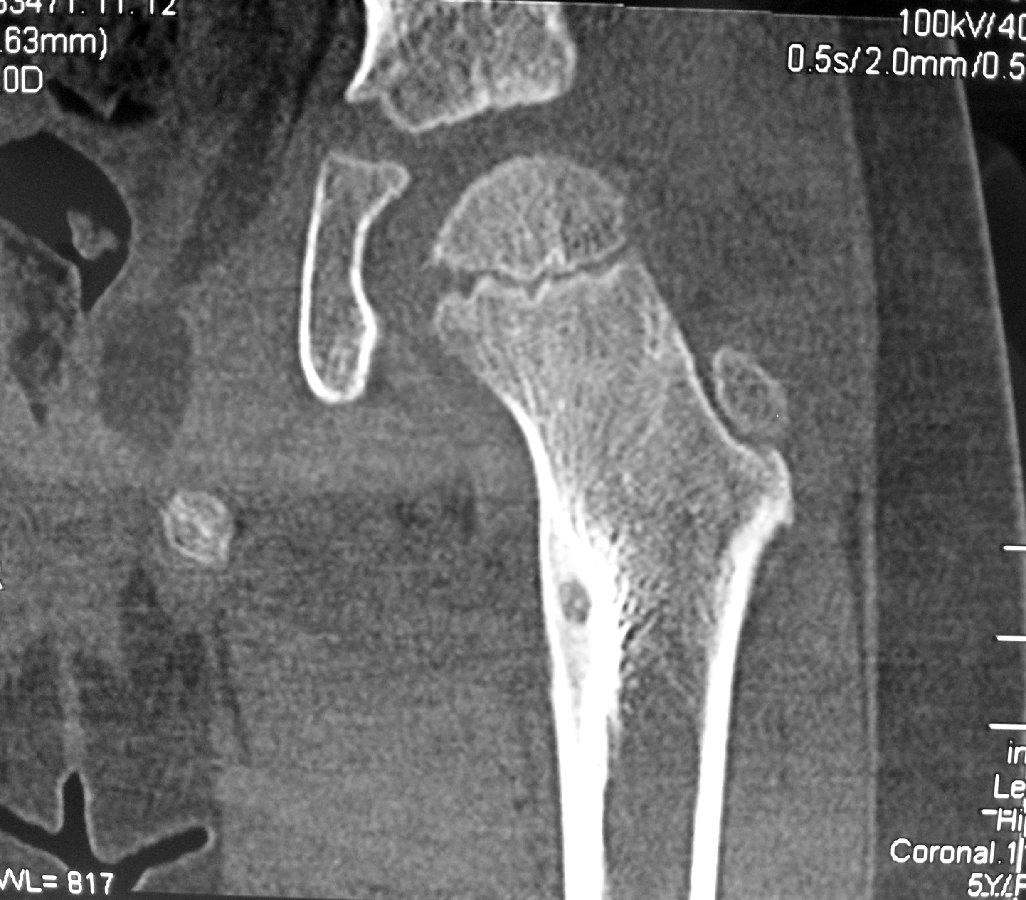

This girl was crying in pain by the time the CT-scans were done. It was obvious that something was wrong. The CT-scan confirmed the presence of an osteoid osteoma of the lesser trochanter of her left hip with pain over her left thigh.

She underwent percutaneous radiofrequency ablation of the tumour under general anaesthesia.

This procedure is done under CT-fluoroscopic guidance.

A 16F needle is inserted through the skin and advanced in a safe zone into the bone of the lesser trochanter under CT-guidance.

The radiofrequency probe is then inserted into the bony tumour.

Correct placement of the radiofrequency probe into the bony tumour lesion is confirmed on CT-scan.

Heat energy is generated by this radiofrequency machine. About 6 minutes worth of energy at 90 degreec Celcius is used to burn the lesion.